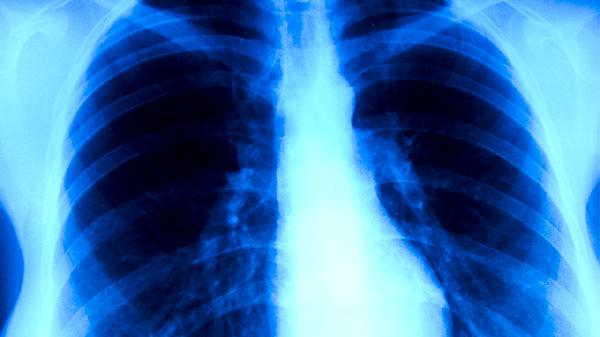

肺结核患者应保持规律作息,每日进行散步、太极拳等温和运动。居室保持20-24℃适宜温度,湿度维持在50%-60%。治疗期间禁止吸烟饮酒,每2周复查肝肾功能。出现视力模糊、关节疼痛等药物不良反应时及时就医,完成6-9个月全程治疗避免复发。康复期可逐渐增加蛋白质和热量摄入,定期进行胸部影像学随访。